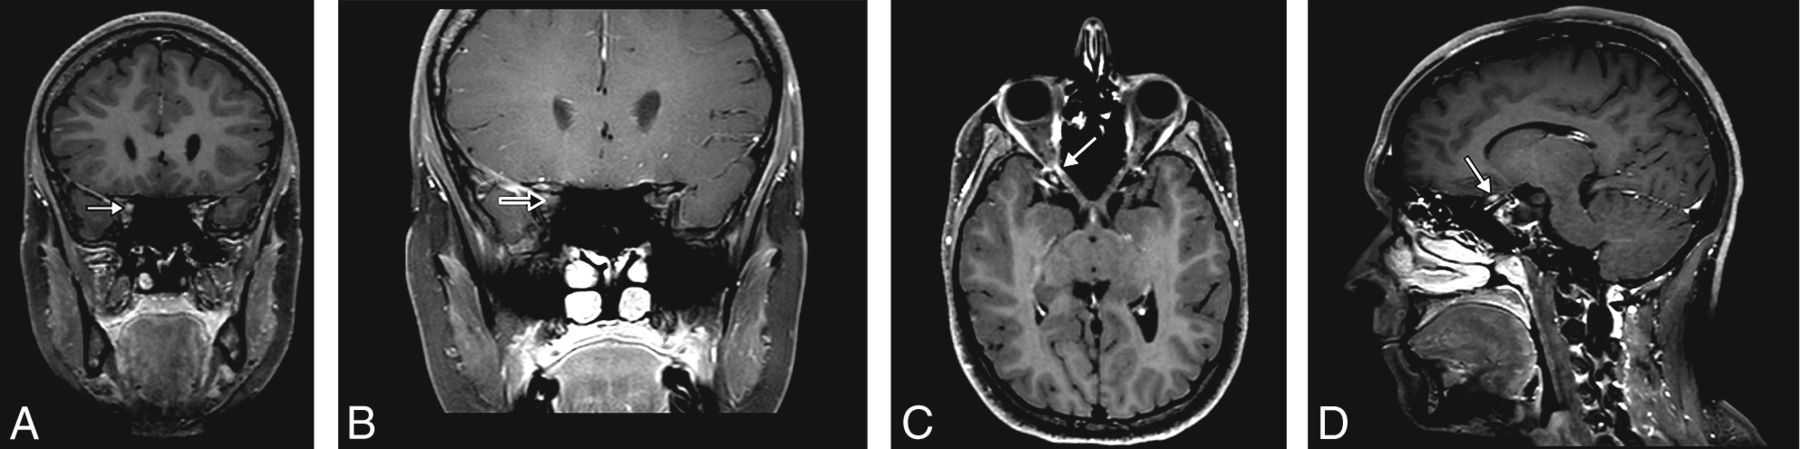

WBCE-3D T1WI was significantly more likely to detect canalicular enhancement compared with OCE-2D T1WI: 108/1023 (10.6%) versus 90/1023 (8.8%) (P = .04), respectively (Fig 1). WBCE-3D T1WI detected 27/1023 (3%) optic disc enhancements versus 0/1023 (0%) on OCE-2D T1WI.

A 21-year-old woman presenting with acute vision loss and orbital pain of the right eye. WBCE-3D TSE T1WI reformatted in the coronal plane (A) shows enhancement of the intraorbital segment of the right optic nerve at the orbital apex (white arrow), whereas no optic nerve enhancement was detected on OCE-2D coronal T1WI (black arrow) (B). The WBCE-3D T1WI sequence reformatted in the axial (C) and sagittal (D) planes confirming and precisely localizing the enhancement of the optic nerve.

Three patients had optic nerve enhancement that was observable on the OCE-2D T1WI sequence but not on the WBCE-3D T1WI sequence.